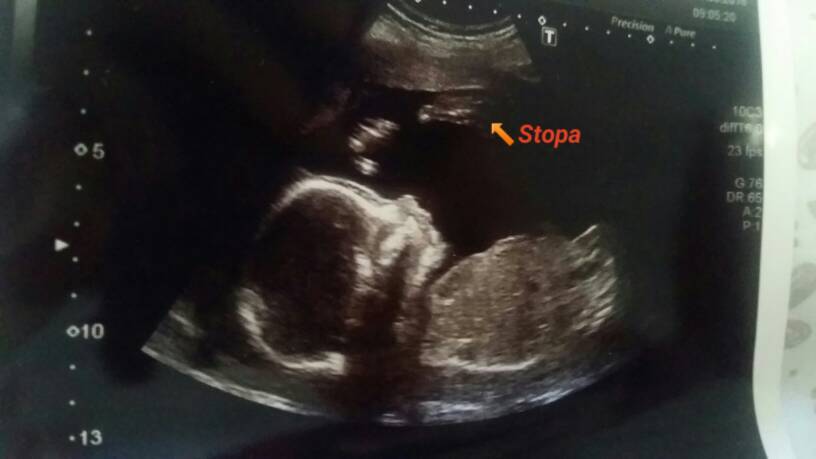

Mała gimnastyczka rośnieNasza wygimnastykowana córeczka [emoji4]Zobacz załącznik 869652Zobacz załącznik 869653